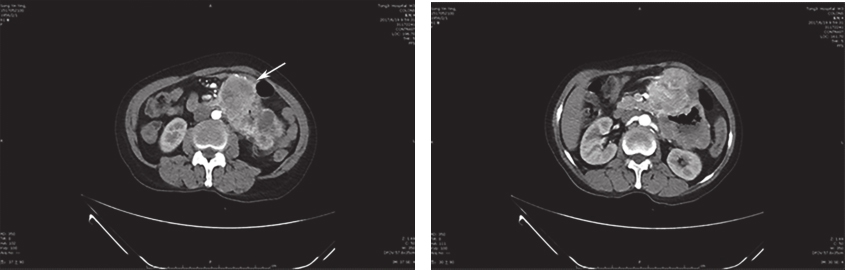

腹部增强CT:近段空肠肠壁明显增厚,可见团块样混杂密度影,最大截面约为10.6cm×7.3cm,动脉期可见明显不均匀强化,由肠系膜上动脉分支供血,多考虑为肿瘤性病变,胃肠间质瘤可能;肝左外叶低密度灶,建议定期复查;盆腔少量积液(图1)。

图1 腹部增强CT

上腹巨大包块与十二指肠分界欠清